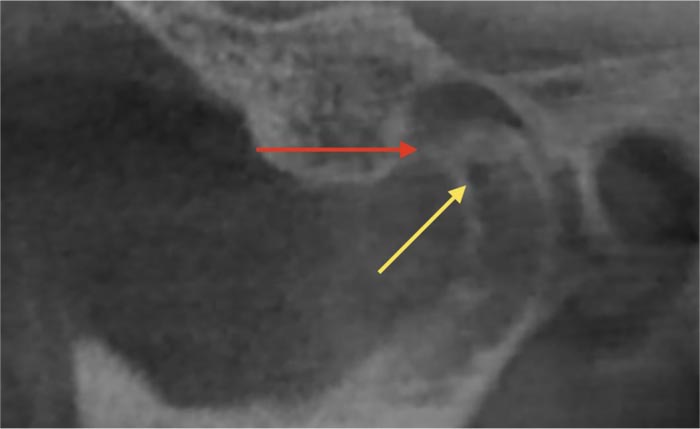

The right and left temporomandibular joints were visualized on sagittal (perpendicular to the longitudinal axis of the condyle), coronal (parallel to the longitudinal axis of the condyle), and axial sections of the joint. The following changes in bone tissue were assessed (Fig. 1 and 2): flattening of the condyle (flat bone contour), erosion (area of reduced density of the cortical bone), sclerosis (area of increased density of the cortical layer), subchondral cysts (osteolytic area of the bone without destruction of the cortical layer), osteophytes (marginal bone outgrowths - exostoses).